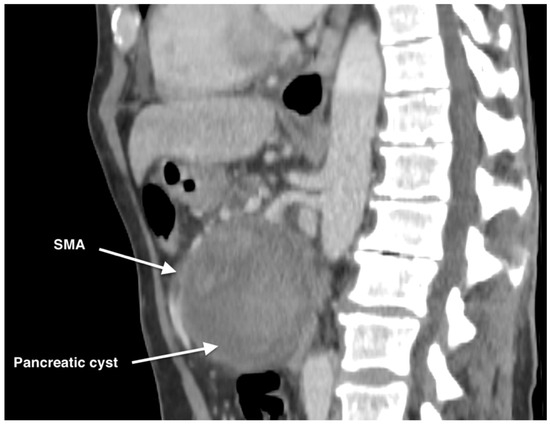

2. Case Report